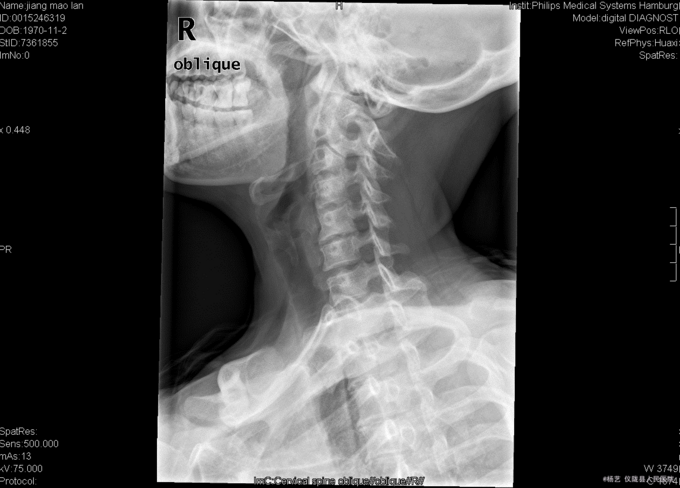

患者蒋茂兰,女,45岁0月,因“头晕伴视物旋转10+月,加重1+月。”入院 10+月前患者无明显诱因出现头晕、头昏;视物旋转,偶伴有呕吐,呕吐为胃内容物;间断发作,发作时持续时间不等,休息后明显缓解。无活动障碍;无肢体麻木、乏力;无行走不稳;无发热、头痛等,1+月前患者上述症状加重,患者于当地医院就诊,治疗未见明显好转。颈椎MRI示:颈5/6椎间盘突出。现患者为求进一步诊治就诊于我院,门诊以“C5/6椎间盘突出症伴脊髓神经不全损害”收入我科。

查体:T:36.9oC,P:78次/分,R:19次/分,BP:109/72mmHg。神志清楚,无病容,皮肤巩膜无黄染,全身浅表淋巴结未见肿大。。颈静脉正常。心界正常,心律齐,各瓣膜区未闻及杂音。胸廓未见异常,双肺叩诊呈清音,双肺呼吸音清,未闻及干湿啰音及胸膜摩擦音。腹部外形正常,全腹柔软,无压痛及反跳痛,腹部未触及包块,肝脏肋下未触及,脾脏肋下未触及,双肾未触及。双下肢无水肿。 专科查体:视:脊柱外观无畸形,活动无异常,无皮肤破溃及窦道形成。触:椎体棘上、椎旁肌无压痛、叩痛,四肢感觉无明显减退,远端血运未见异常。动量:颈部屈伸、左右侧偏活动无明显受限,双上肢耸肩、屈伸肘关节、屈伸腕肌力5级,双手握力5级,双下肢伸髋、屈髋、外展、内收、伸膝、屈膝肌力5级,双足趾背伸肌力5级。双侧肱二、三头肌肌腱反射、膝腱反射、跟腱反射正常引出。双侧Hoffmann氏征阳性,Babinski征阴性,踝阵挛阴性,髌阵挛阴性。 辅助检查:外院MRI示:颈椎退行性变,颈5/6椎间盘突出。垂体区:空泡蝶鞍?

综上初步诊断:1、颈5-6椎间盘突出症伴脊髓神经不全损害;2、白癜风 经前路颈5/6椎间盘切除、椎管及椎间孔减压、椎间融合器植骨融合内固定术。 手术发现:  颈5/6椎间隙变窄,椎间盘髓核干涩,无光泽。颈5/6椎间隙后份少量骨赘生成,椎间盘向后方突出,压迫硬脊膜。术中夹出数块突入椎管内的椎间盘髓核组织及增生骨赘。充分减压后,可见硬脊膜恢复膨隆,双侧神经根松弛,术中未见脑脊液漏。